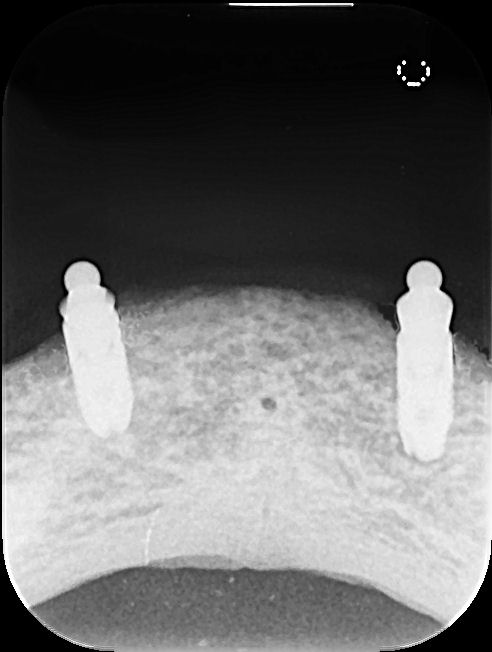

上顎欠損 抜歯即時埋入

治療後レントゲン写真